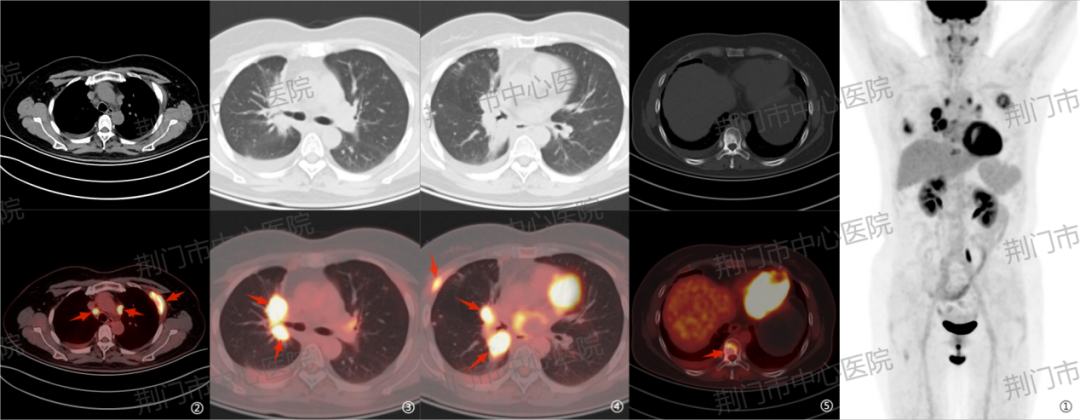

病例四:右肺癌综合治疗后 3 年余,患者出现右侧胸背部间断疼痛 4 月余。PET/CT 显示右肺近肺门区、胸 9 椎体及右侧附件病灶代谢增高,提示活性残留;同时发现多个新发转移灶,提示疾病进展。